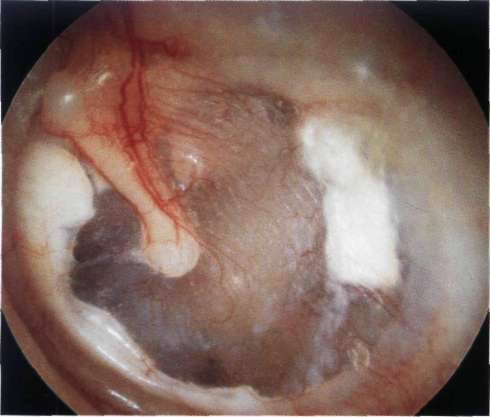

Colesteatoma